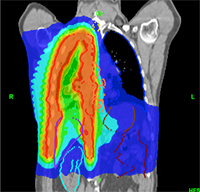

Η ακτινοθεραπεία χρησιμοποιεί υψηλής ενέργειας ακτίνες Χ, για να σκοτώσει τα καρκινικά κύτταρα. Οι κυριότερες τεχνικές ακτινοθεραπείας που χρησιμοποιούνται είναι η εξωτερική ακτινοθεραπεία που αποτελείται από τη τρισδιάστατη σύμμορφο ακτινοθεραπεία (3D-CRT), τη διαμορφούμενης έντασης ακτινοθεραπεία ( IMRT) και την απεικονιστικά καθοδηγούμενη ακτινοθεραπεία( IGRT).Σε όγκους σταδίου Ι,ΙΙ χρησιμοποιείται η στερεοτακτική ακτινοθεραπεία με αποτελέσματα ισάξια της χειρουργικής αφαίρεσης. Αυτή η μορφή της ακτινοβολίας στοχεύει πολλές ακτίνες ακτινοβολίας από διαφορετικές γωνίες στο καρκίνο του πνεύμονα. Η θεραπεία ολοκληρώνεται σε 1-3 συνεδρίες.

1. Προεγχειρητική ακτινοθεραπεία: χρησιμοποιείται για τη σμίκρυνση του όγκου, ώστε να γίνει η χειρουργική αφαίρεση του εύκολη.

2. Μετεγχειρητική ακτινοθεραπεία: εφαρμόζεται μετά τη χειρουργική αφαίρεση του όγκου. Η σκοπιμότητά της είναι η αποστείρωση της περιοχής από τυχόν υπολειμματικά καρκινικά κύτταρα.

3. Ριζική ακτινοθεραπεία Επιλέγεται σαν αρχική θεραπεία σε χειρουργήσιμη νόσο σταδίων Ι,ΙΙ,ΙΙΙ σε ασθενείς που δεν είναι εφικτό ή αρνούνται να υποβληθούν σε χειρουργική αφαίρεση. Σε όγκους τοπικά προχωρημένους σταδίου ΙΙΙ με ή χωρίς νόσο στους λεμφαδένες.η ακτινοθεραπεία είναι πολύ αποτελεσματική, ιδιαίτερα όταν συνδυάζεται με τη χημειοθεραπεία, ιδίως σε άτομα που πάσχουν από μη μικροκυτταρικό καρκίνο του πνεύμονα.